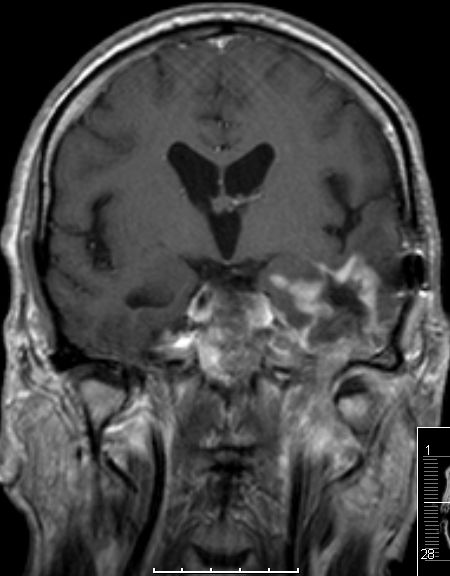

Glioblastome metastasieren normalerweise nicht außerhalb des ZNS. | |

| Fall | Im vorliegenden Fall kam es während der Temodal-Therapie nach postoperativer Radiochemotherapie zu einen Durchbruch des GBs durch die Schädelbasis. | |